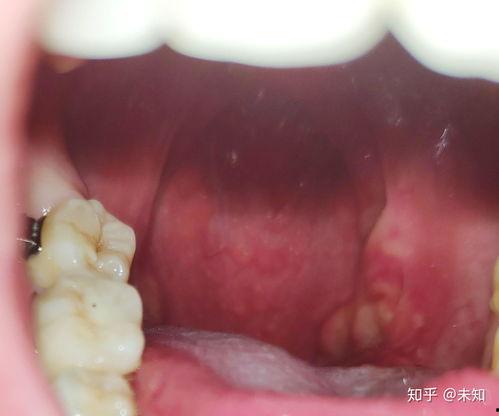

那么,为什么扁桃体摘除会成为明星们的“痛”呢?其实,这主要是因为扁桃体发炎导致的。扁桃体是人体免疫系统的一部分,位于喉咙两侧,主要负责抵御病原体。当人体抵抗力下降时,扁桃体就会发炎,引发喉咙痛、发烧等症状。